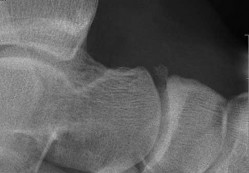

Prepare for the Arab Orthopaedic Board exam with high-yield MCQs, clinical cases, and comprehensive review materials.